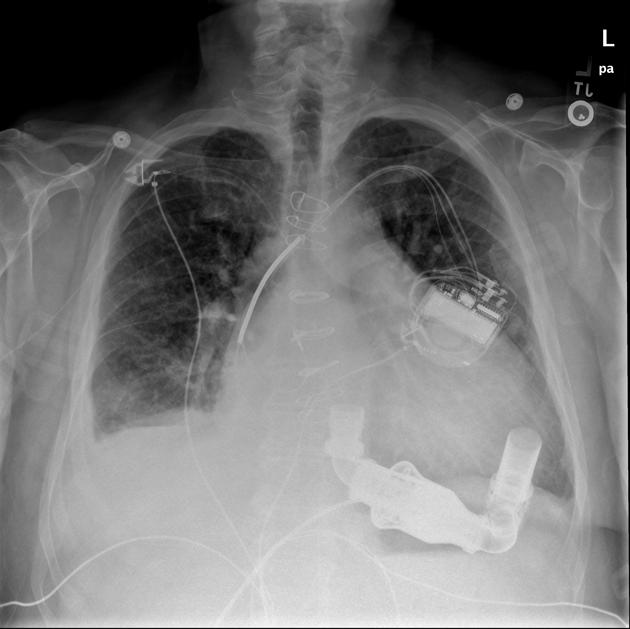

24.下圖是一位加護病房中狀況穩定的心臟疾病患者之X光影像,下列敘述何項正確?

(A)紅色箭號所指裝置是左心室輔助器(LVAD)

(B)患者須臥床,不能進行床邊運動

(C)患者右側髖部不能彎曲

(D)紅色箭號所指裝置可以增加心肌灌流